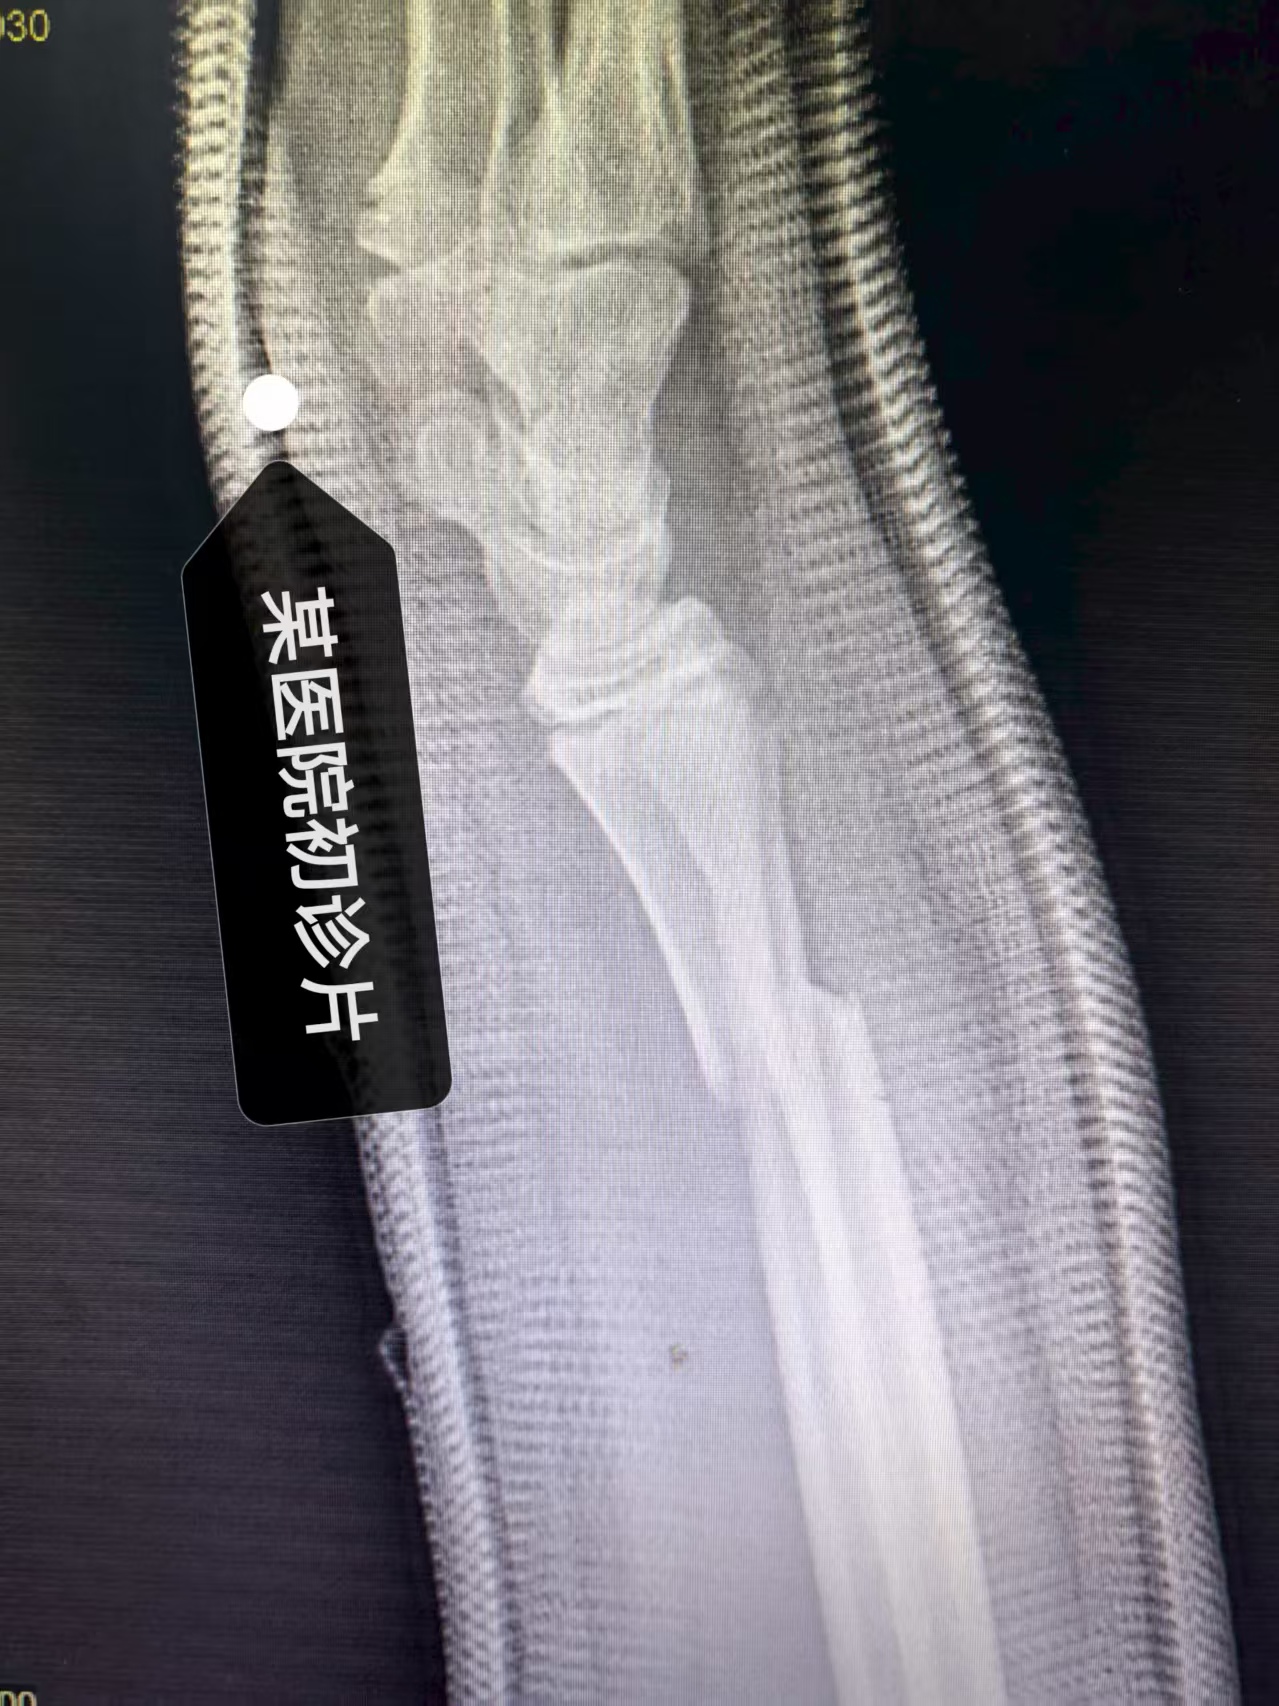

(上面二图,是患者在某大医院初诊,经复位加石膏外固定后,建议手术前照片)